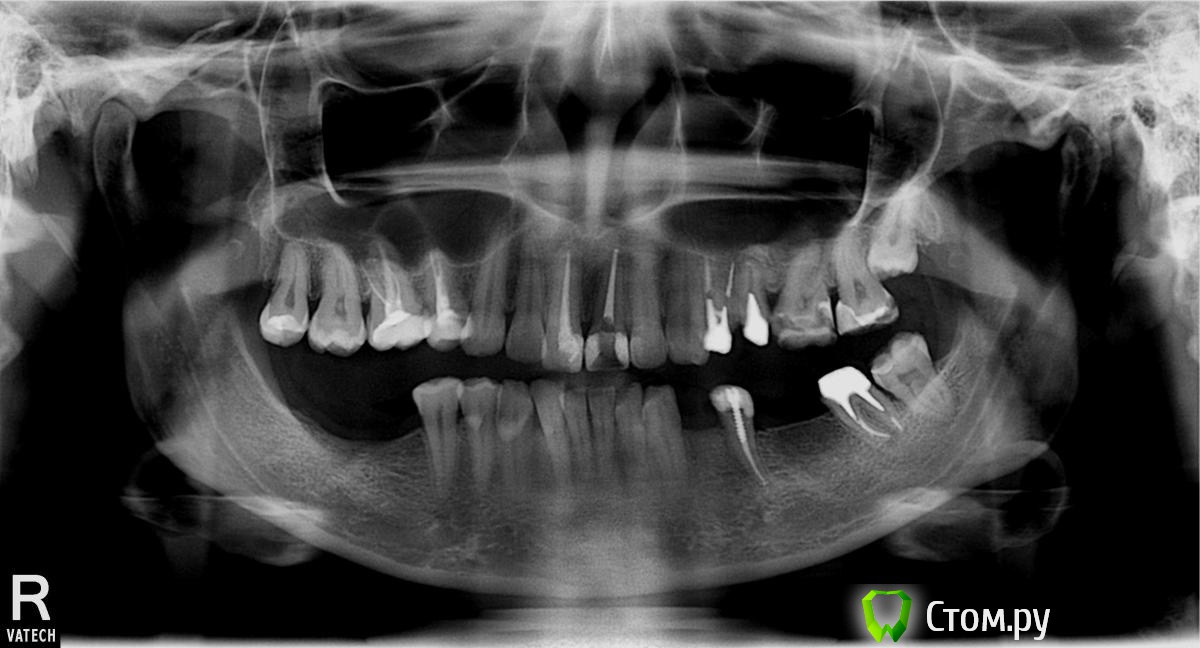

dextrilla Опубликовано 22 января, 2014 Поделиться Опубликовано 22 января, 2014 Здравствуйте! Врач рекомендует делать интрузию зубов 7 и 6 слева. Другой рекомендовал ставить съемные протезы на время лечения, чтобы зубы не опускались. Третий сказал, что надо просто ставить брекеты и все. Я теперь на перепутье. Подскажите, пожалуйста, как лучше сделать? Ссылка на комментарий

Art 7 Опубликовано 22 января, 2014 Поделиться Опубликовано 22 января, 2014 хорошо бы модели челюстей посмотреть чтобы видно было для чего делать интрузию, и каков план лечения Вашего доктора в целом чтобы понять целесообразность перемещений, но в любом случае от съёмных лучше отказаться сразу 1 Ссылка на комментарий